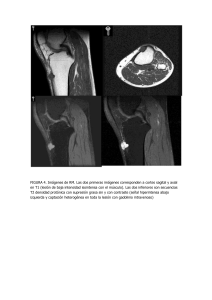

FIGURA 4. Imágenes de RM. Las dos primeras imágenes